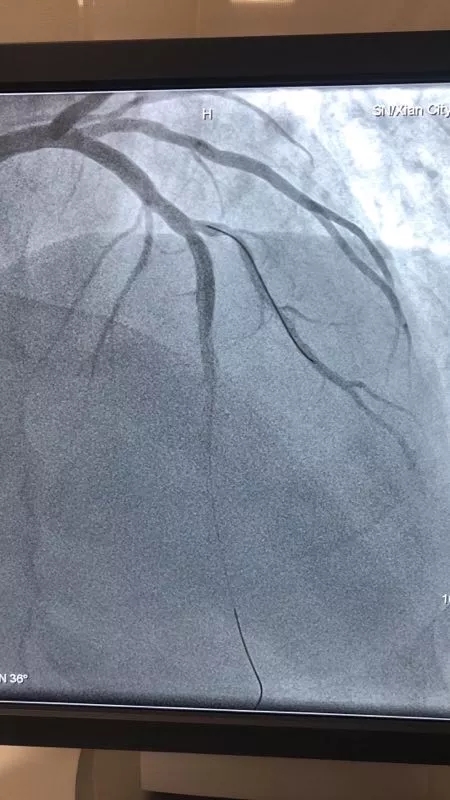

CCU病区成功实施冠脉药物涂层球囊扩张术 治疗支架内再狭窄